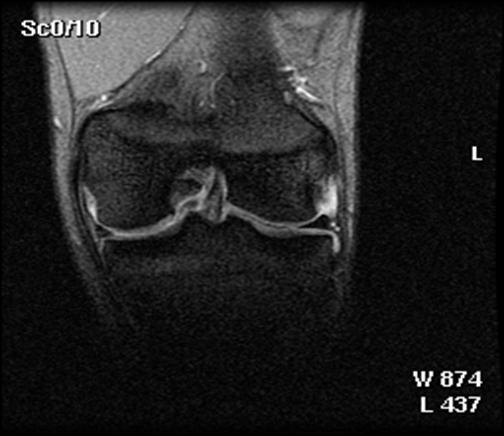

1. Imaginile RMN

Din 48 de pacienti tratati cu tehnica de microfracturare in studiul nostru , 24 (50%) au acceptat sa fie evaluati prin imagini ale rezonantei magnetice. RMN a fost facuta doar pentru studiu si nu datorita vreunui simptom clinic si s-a efectuat in medie la 12 2 luni (de la 3 la 36 de luni) dupa operatie. Imaginile au fost executate la mai putin de 6 luni pentru 3 pacienti (13%), de la 6 la 12 luni pentru 15 pacienti (61%) si mai mult de 12 luni dupa microfracturi pentru 6 pacienti (26%). Sase pacienti au o serie de imagini RMN cu media 1,3 0,1 (de la 1 la 3 scanari) pe pacient. La acesti 6 pacienti, descoperirile la cea mai recenta evaluare imagistica au fost folosite pentru analiza rezultatelor functionale. Nu s-au gasit diferente semnificative intre pacientii cu sau fara evaluare imagistica RMN cu privire la datele demografice (p> 0,650); caracteristicile leziunilor (p>0,450); durata preoperatorie a simptomelor (p= 0,793); indexul masei corporale (p= 0,217); durata urmarii postoperatorii (p= 0,902); si scorul preoperator si postoperator pentru activitatile zilnice(p=0,250); SF-36componenta fizica (p= 0,250), IKDC (p= 0,820) si rata subiectiva (p = 0,867).

Fig.32. Imagine RMN pacient T.C. 19 ani

Fig.33. Imagine RMN T.C. 19 ani

Fig.34. A-scanare inaintea microfracturarii, B-scanare la patru luni dupaa microfracturare.

Evaluarea imaginilor RMN a fost realizata de catre radiologist cu experienta, care cunostea situatia pacientilor si operatia efectuata. Imaginile au fost astfel analizate incat sa se observe zonele cu cartilaj de reparare comparativ cu cel nativ. Repararea morfologica a fost descrisa ca depresiva, neteda, sau mareata comparativ cu cartilajul nativ inconjurator. Volumul de umplere al defectului cu cartilaj reparator a fost masurat folosind imagini sagitale si coronale si a fost gradat ca bun (intre 67% si 100%), moderat (34% la 66%), sau slab (0% la 33%) pe baza procentajului defectului umplut. Interfata cu suprafata cartilajului nativ adiacent a fost evaluata si gradata ca fiind mica ( gaura ≤ 2mm) sau mare (gaura ˃ 2mm). Edemul maduvei osului subcondral a fost gradat ca fiind usor (˂ 1 cm²), moderat (intre 1 si 3 cm²) sau sever (˃ 3 cm²), iar prezenta sau absenta cresterii osoase a fost atent inregistrata.